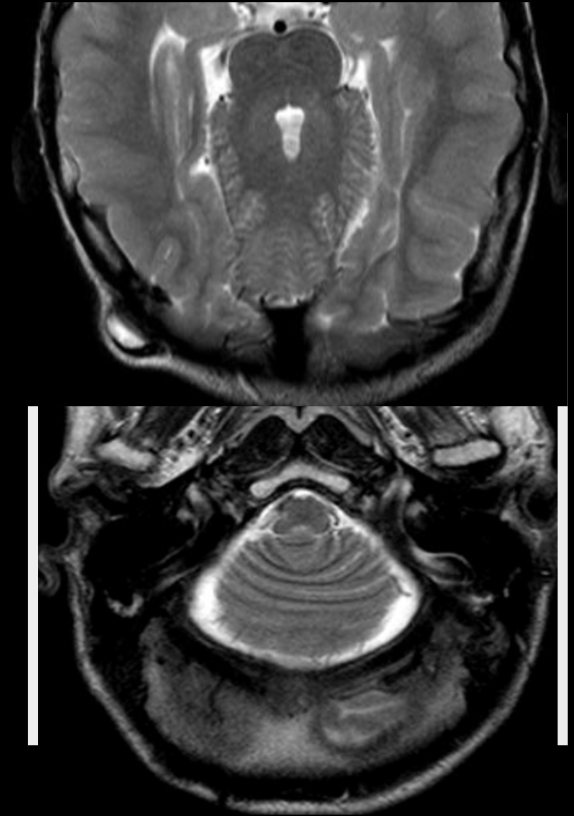

What is rhombencephalosynapsis.

Name 2 imaging features and 1 association

Definition: congenital/developmental agenesis/hypogenesis of the cerebellar vermis, and dorsal fusion of the cerebellar hemispheres, dentate nuclei and cerebellar peduncles

Imaging features:

- as above

- diamond/keyhole shaped 4th ventricle on axial imaging

- horizontal cerebellar folia

- may have hydrocephalus (secondary to aqueductal stenosis)

Associations:

- VACTERL